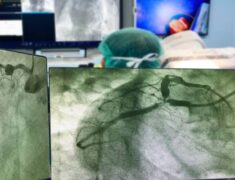

Pioneering Heart Disease Diagnosis Coronary Angiogram

Chennai shines in medical milestones, especially heart health diagnostics, with its leap in coronary angiogram technology. This leading-edge procedure, powered by CT angiography, brings hope and fresh avenues for those at a greater risk of heart-related issues. It is a boon for adults and fitness buffs keen on heart health, offering quick and precise